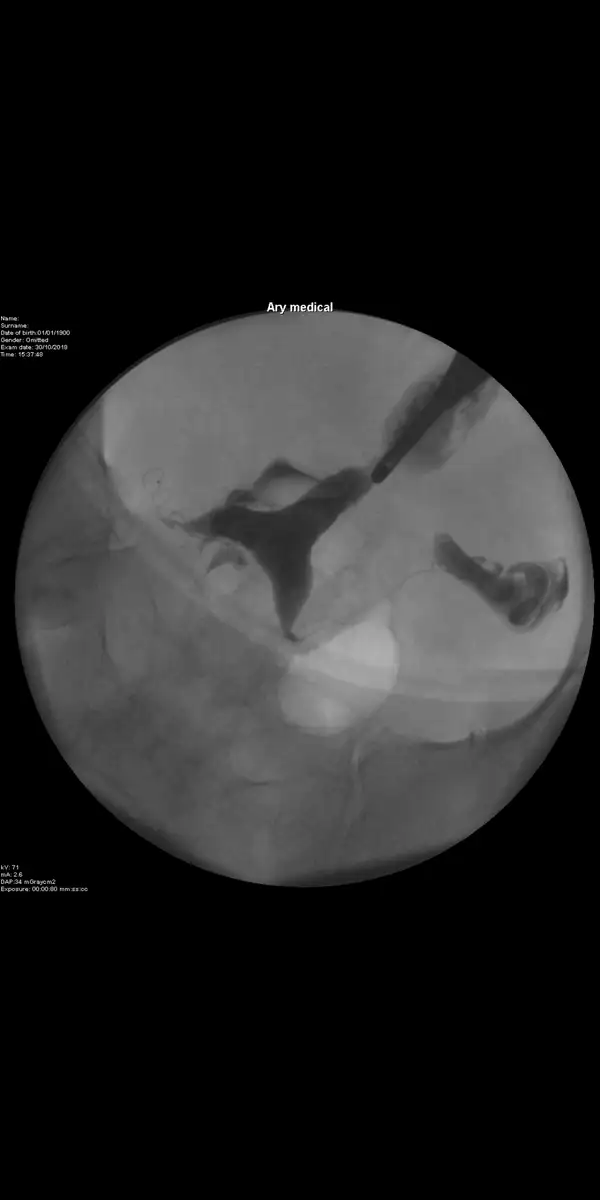

Çok geçmiş olsun canım peki şöyle bi durum olabilir mi anestezisiz çekimlerde hasta kendini sıkıp kasma durumlarında yanıltıcı sonuçlar çıkabiliyormuş o yüzden öyle çıkmıştır belki seninki de çok geçmiş olsun buaradaBnim rahmimde zar olduğu için bi tüpüm bile gözükmedi. Hatta yarım rahim olarak gözükmüş filmde. O yüzden felaket acıdı. Bir daha çekincem zar alındıktan sonra.

Anladım canım hakkımız da hayırlısı olsun hepimizindeCanım benim durumum farklı biraz. Septum var bnde yani rahimdr zar var ve rahmi 2 ye bölmüş rahmin diğer tarafına giremedi dr ve acayip acıdı bu yüzden.

Gecen hafta çektirdim Sifir aci olmasa da dayanılmayacak bir aci degildi Bugün sonucu oldum kanallar acik fakat uterusta sola deviye var yaziyor. Doktora sordum sorun olmaz dedi ama emın olmadim. Bir sorun olur mu sizin bilginiz var miCanım çektirmişsindir muhtemelen ama bende çektirdim neredeyse sıfır acı ve kıpırdama durumu olmadı dolayısıyla